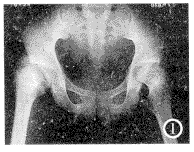

X线表现 左、右髋关节片:双侧股骨头骨骺和骨干近端呈不同程度之脱离。主要显示为双侧股骨颈明显上移,尤以右侧为甚。右侧股骨颈严重上移,与轻度外翻的股骨头完全重叠。大粗隆内上方与髋臼外上缘重叠,小粗隆部分与股骨头内下缘重叠。左侧股骨头较右侧小,并示内侧向上外翻,其外侧向下移与大粗隆部分重叠。双股骨头、股骨颈密度均减低。余无明显异见。X线诊断:双侧股骨头骨骺滑脱(图1)。

图1 右侧股骨颈明显上移,与轻度外翻的股骨头骨骺严重重叠。

左侧股骨头向上外翻,股骨颈上移。